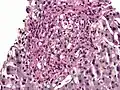

PAS diastase showing Histoplasma in a liver biopsy.

Periodic acid–Schiff–diastase (PAS-D, PAS diastase) stain is a periodic acid–Schiff (PAS) stain used in combination with diastase, an enzyme that breaks down glycogen. PAS-D is a stain often used by pathologists as an ancillary study in making a histologic diagnosis on paraffin-embedded tissue specimens. PAS stain typically gives a magenta color in the presence of glycogen. When PAS and diastase are used together, a light pink color replaces the deep magenta. Differences in the intensities of the two stains (PAS and PAS-D) can be attributed to different glycogen concentrations and can be used to semiquantify glycogen in samples. In practice, the tissue is deparaffinized, the diastase incubates, and then the PAS stain is applied.

An example of PAS-D in use is in showing gastric/duodenal metaplasia in duodenal adenomas.[1] PAS diastase stain is also used to identify alpha-1 antitrypsin globules in hepatocytes, which is a characteristic finding of alpha-1 antitrypsin deficiency.[2] PAS diastase stain is also used in diagnosing Whipple’s disease, as the foamy macrophages that infiltrate the lamina propria of the small intestine in this disease possess PAS-positive, diastase-resistant inclusions.[3]